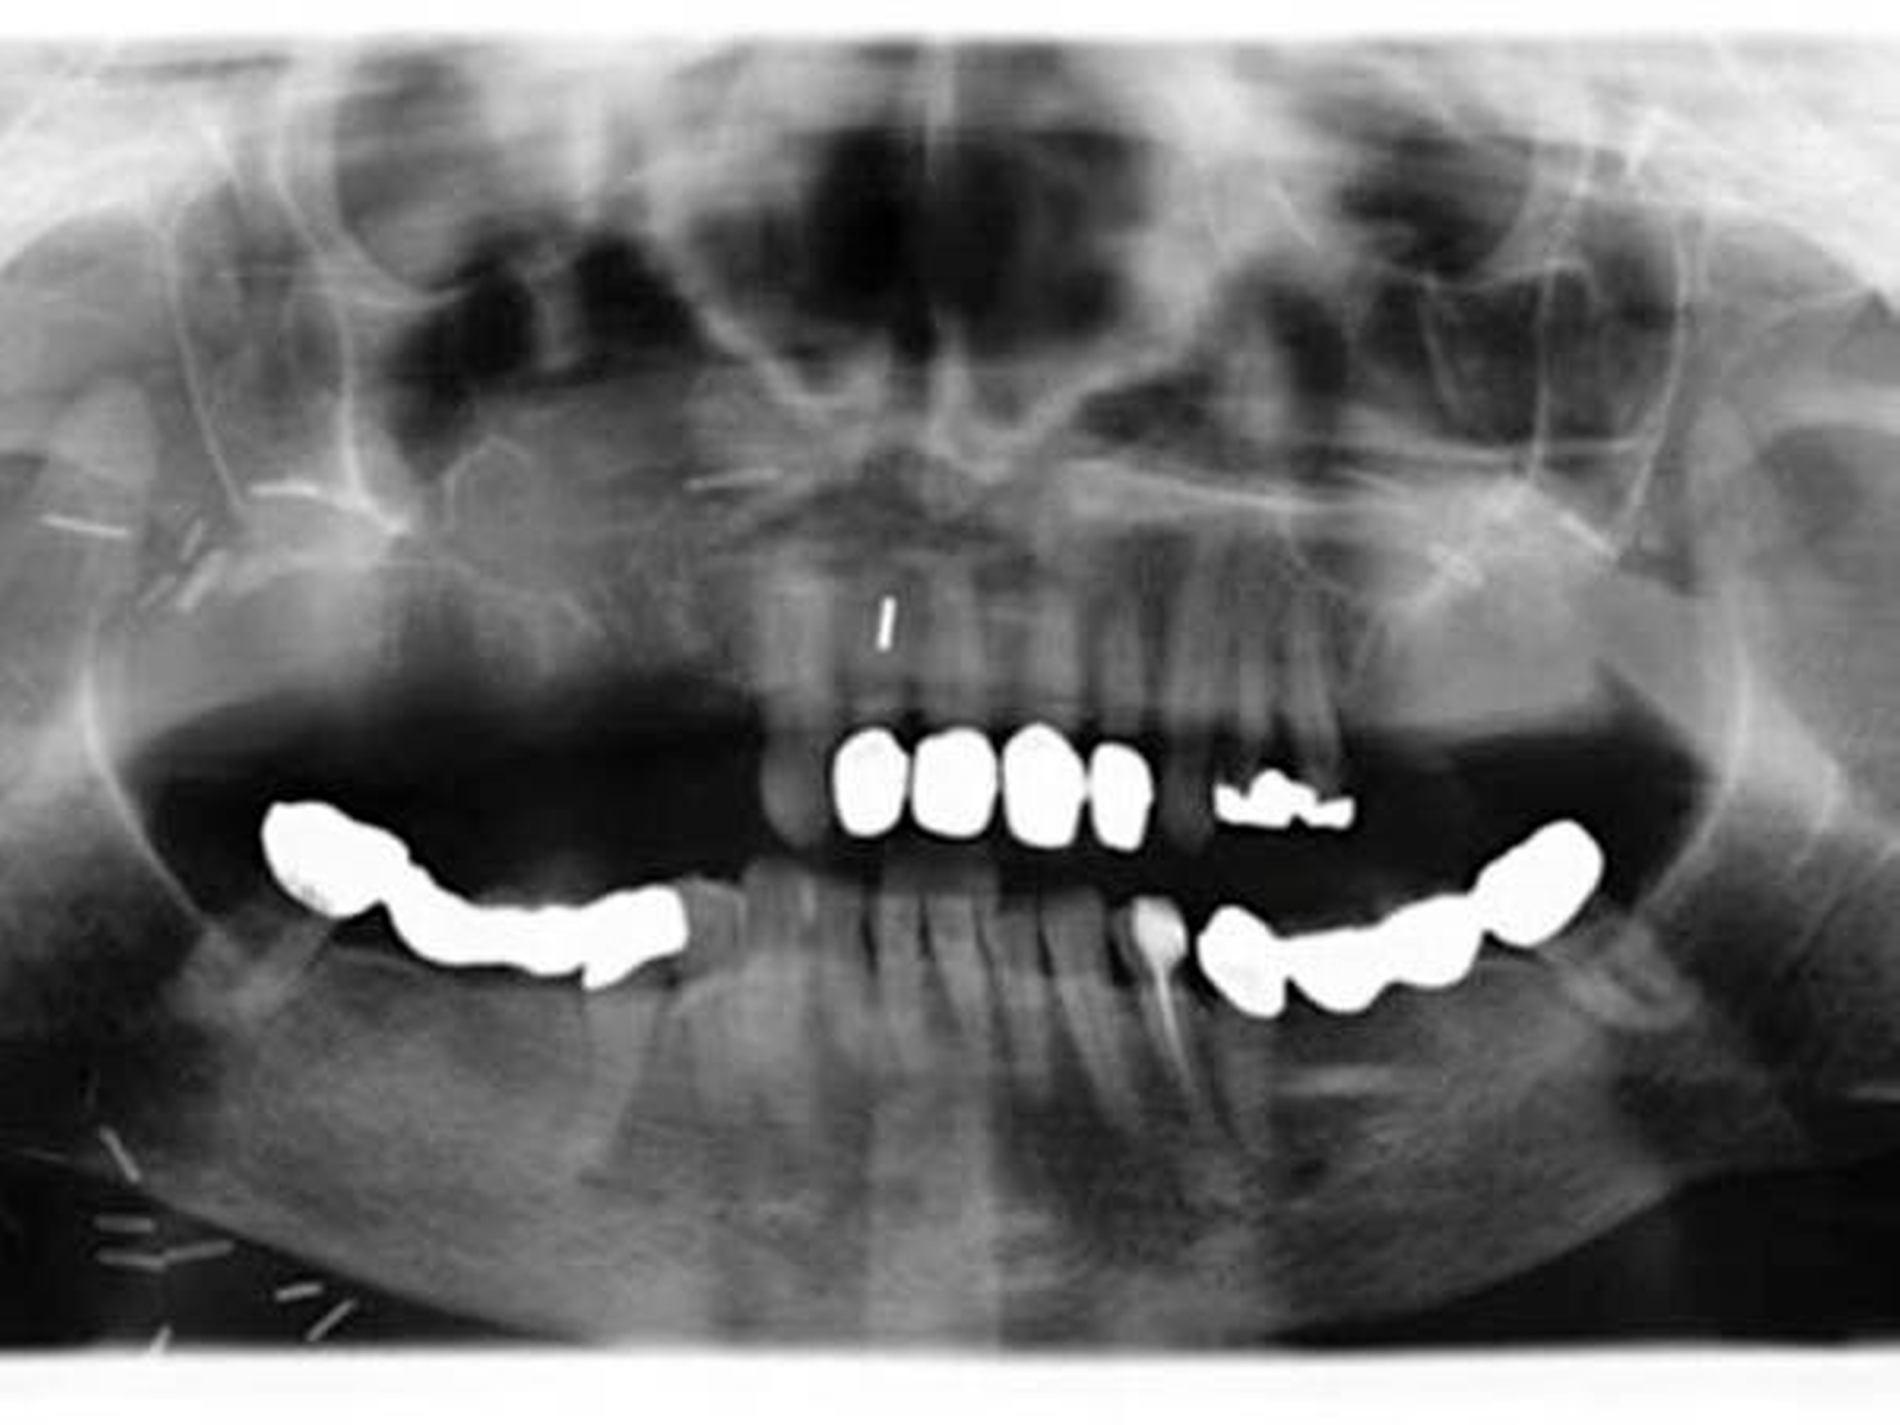

Der postoperative Verlauf der Patientin gestaltete sich problemlos. Die Trachealkanüle konnte nach Abschwellen am dritten postoperativen Tag entfernt werden. Schlucken und Sprechen waren sofort gut möglich. Das Lappentransplantat war zu jeder Zeit gut vaskularisiert und seine Grenzen dicht. Die Nasenatmung war nicht mehr gestört.

Bei Ausgang des Tumors von den kleinen Speicheldrüsen im Bereich des harten Gaumens und in Zusammenschau mit den üblichen Staging-Untersuchungen ergibt sich folgende postoperative Tumorklassifikation [TNM 8. Auflage 2017]: pT3, pN1(1/6), M0, L0, V0, Stadium III, Differenzierungsgrad G1, R1.

Die Patientin stellt sich regelmäßig und engmaschig in unserer Tumorsprechstunde zur Nachsorge vor, die regelmäßige klinische und radiologische Kontrollen umfasst.